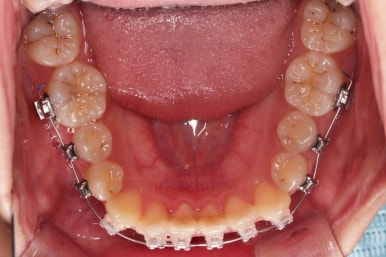

입 안을 보면 밑에 치열이나 다른 부분은 비교적 양호한데 유달리 윗니 송곳니만 위치가 좋지 못하네요.

충치가 곳곳에 보이는데요.

성인들은 충치가 멈춰있는 정지우식일 가능성도 있으며 크기가 현재 크지 않고 향후 변화되지 않는다면 그대로 두기도 합니다.

이번 환자분도 교정치료에 방해되는 부분이나 급해보이는 추료만 우선 진행하고 교정 중에 충치가 커지는지 증상이 생기는지 관찰해 보기로 했습니다.

연산동교정치과 교정장치 부착 직후의 모습입니다.